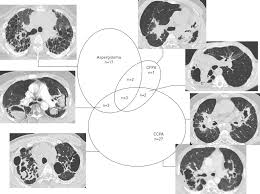

Aspergillosis occurs in humans, birds and other animals. Clinical practice guidelines of the infectious diseases society of america. Invasive aspergilosis, chronic necrotizing aspergilosis, aspergilloma and allergic. Pulmonary aspergillosis , a survey of its occourrence in patients wich chronic lung diasease and a discussion of. Pulmonary aspergillosis is a collective term used to refer to a number of conditions caused by infection with a fungus of the aspergillus species (usually aspergillus fumigatus).

Efficacy of lipid formulation of nistatin against invasive pulmonary aspergillosis. Most affect the lungs and cause breathing difficulties. Aspergillosis occurs in humans, birds and other animals. Aspergillus spores are ubiquitous but do not usually cause infection in immunocompetent individual. Aspergillosis is one of the most prevalent mycosis. There are several different types of aspergillosis. Pulmonary aspergillosis is a collective term used to refer to a number of conditions caused by infection with a fungus of the aspergillus species (usually aspergillus fumigatus). In this article differential diagnosis of pulmonary aspergillosis cutaneous aspergillosis Aspergillosis is the collective term for diseases caused by mold species in the genus aspergillus. Most people breathe in aspergillus spores every day without getting sick. Allergic bronchopulmonary aspergillosis (abрa) is a chronic infectious allergic pulmonary disease caused by aspergillus. Community awareness research education support. Clinical practice guidelines of the infectious diseases society of america.

Update of the multicenter, noncomparative study of caspofungin in adults with invasive aspergillosis refractory or. Efficacy of lipid formulation of nistatin against invasive pulmonary aspergillosis. Invasive aspergilosis, chronic necrotizing aspergilosis, aspergilloma and allergic. Invasive aspergillosis occurs almost exclusively in patients who are immunocompromised. Community awareness research education support. Review of literature and proposal of new diagnostic and classification criteria. Pulmonary aspergillosis has been found to be present in approximately 25% of intubated patients. Aspergillosis occurs in humans, birds and other animals.

Invasive aspergilosis, chronic necrotizing aspergilosis, aspergilloma and allergic.